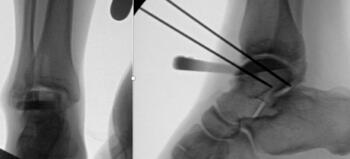

We presented the option of a patient-specific partial talar replacement with a plan to resect and replace the entire lateral shoulder. As part of the design process, the implant had custom cut guides that would sit on the talar neck, temporarily secured in place with smooth wires. This guide would then correlate with the final implants to ensure the appropriate amount of bone removal and allow more accurate bone resection. In addition, the design incorporated two stems in the final implant to add stability and fixation surface area. Three sizes of implant allowed intra-operative flexibility.

The incision was the typical anterior ankle approach. This would limit location of incisions for potential future issues or conversion to fusion or total implant. We then exposed the distal tibia and dorsal neck of the talus. Placing the prefabricated custom cut guide onto the neck of the talus, we then checked this under fluoroscopy to ensure placement, and the proper orientation and amount of lateral dome to be removed. We then pinned this guide in place with predetermined holes. A reciprocating blade limited blade excursion and minimized potential for injury to adjacent structures. After removal of the damaged piece of talus we placed the trials. The goal was to have the trial flush or even slightly recessed with regard to the adjacent cartilage. During weight bearing, the native cartilage will compress, so it is important to match the weight bearing level. If the implant is proud, then during weight bearing the cartilage will naturally compress, but the implant will not, potentially giving rise to issues with load bearing around the device.